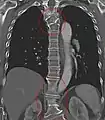

Several congenital block vertebrae in the transition from the thoracic to the lumbar spine and hemivertebrae.

Congenital block vertebra of the lumbar spine. CT volume rendering.